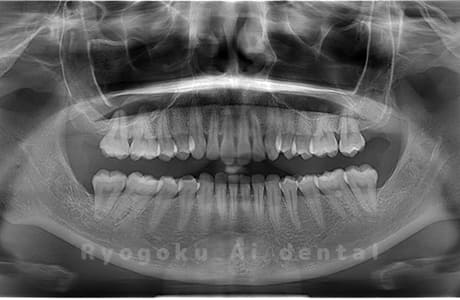

Case03

- 原因

- 上顎、下顎の親知らず

- 治療内容

- 上下4本の親知らずを抜歯したケースです。

<リスク・副作用>

手術後は痛み、腫れ、痺れなどの副作用が生じる場合があります。